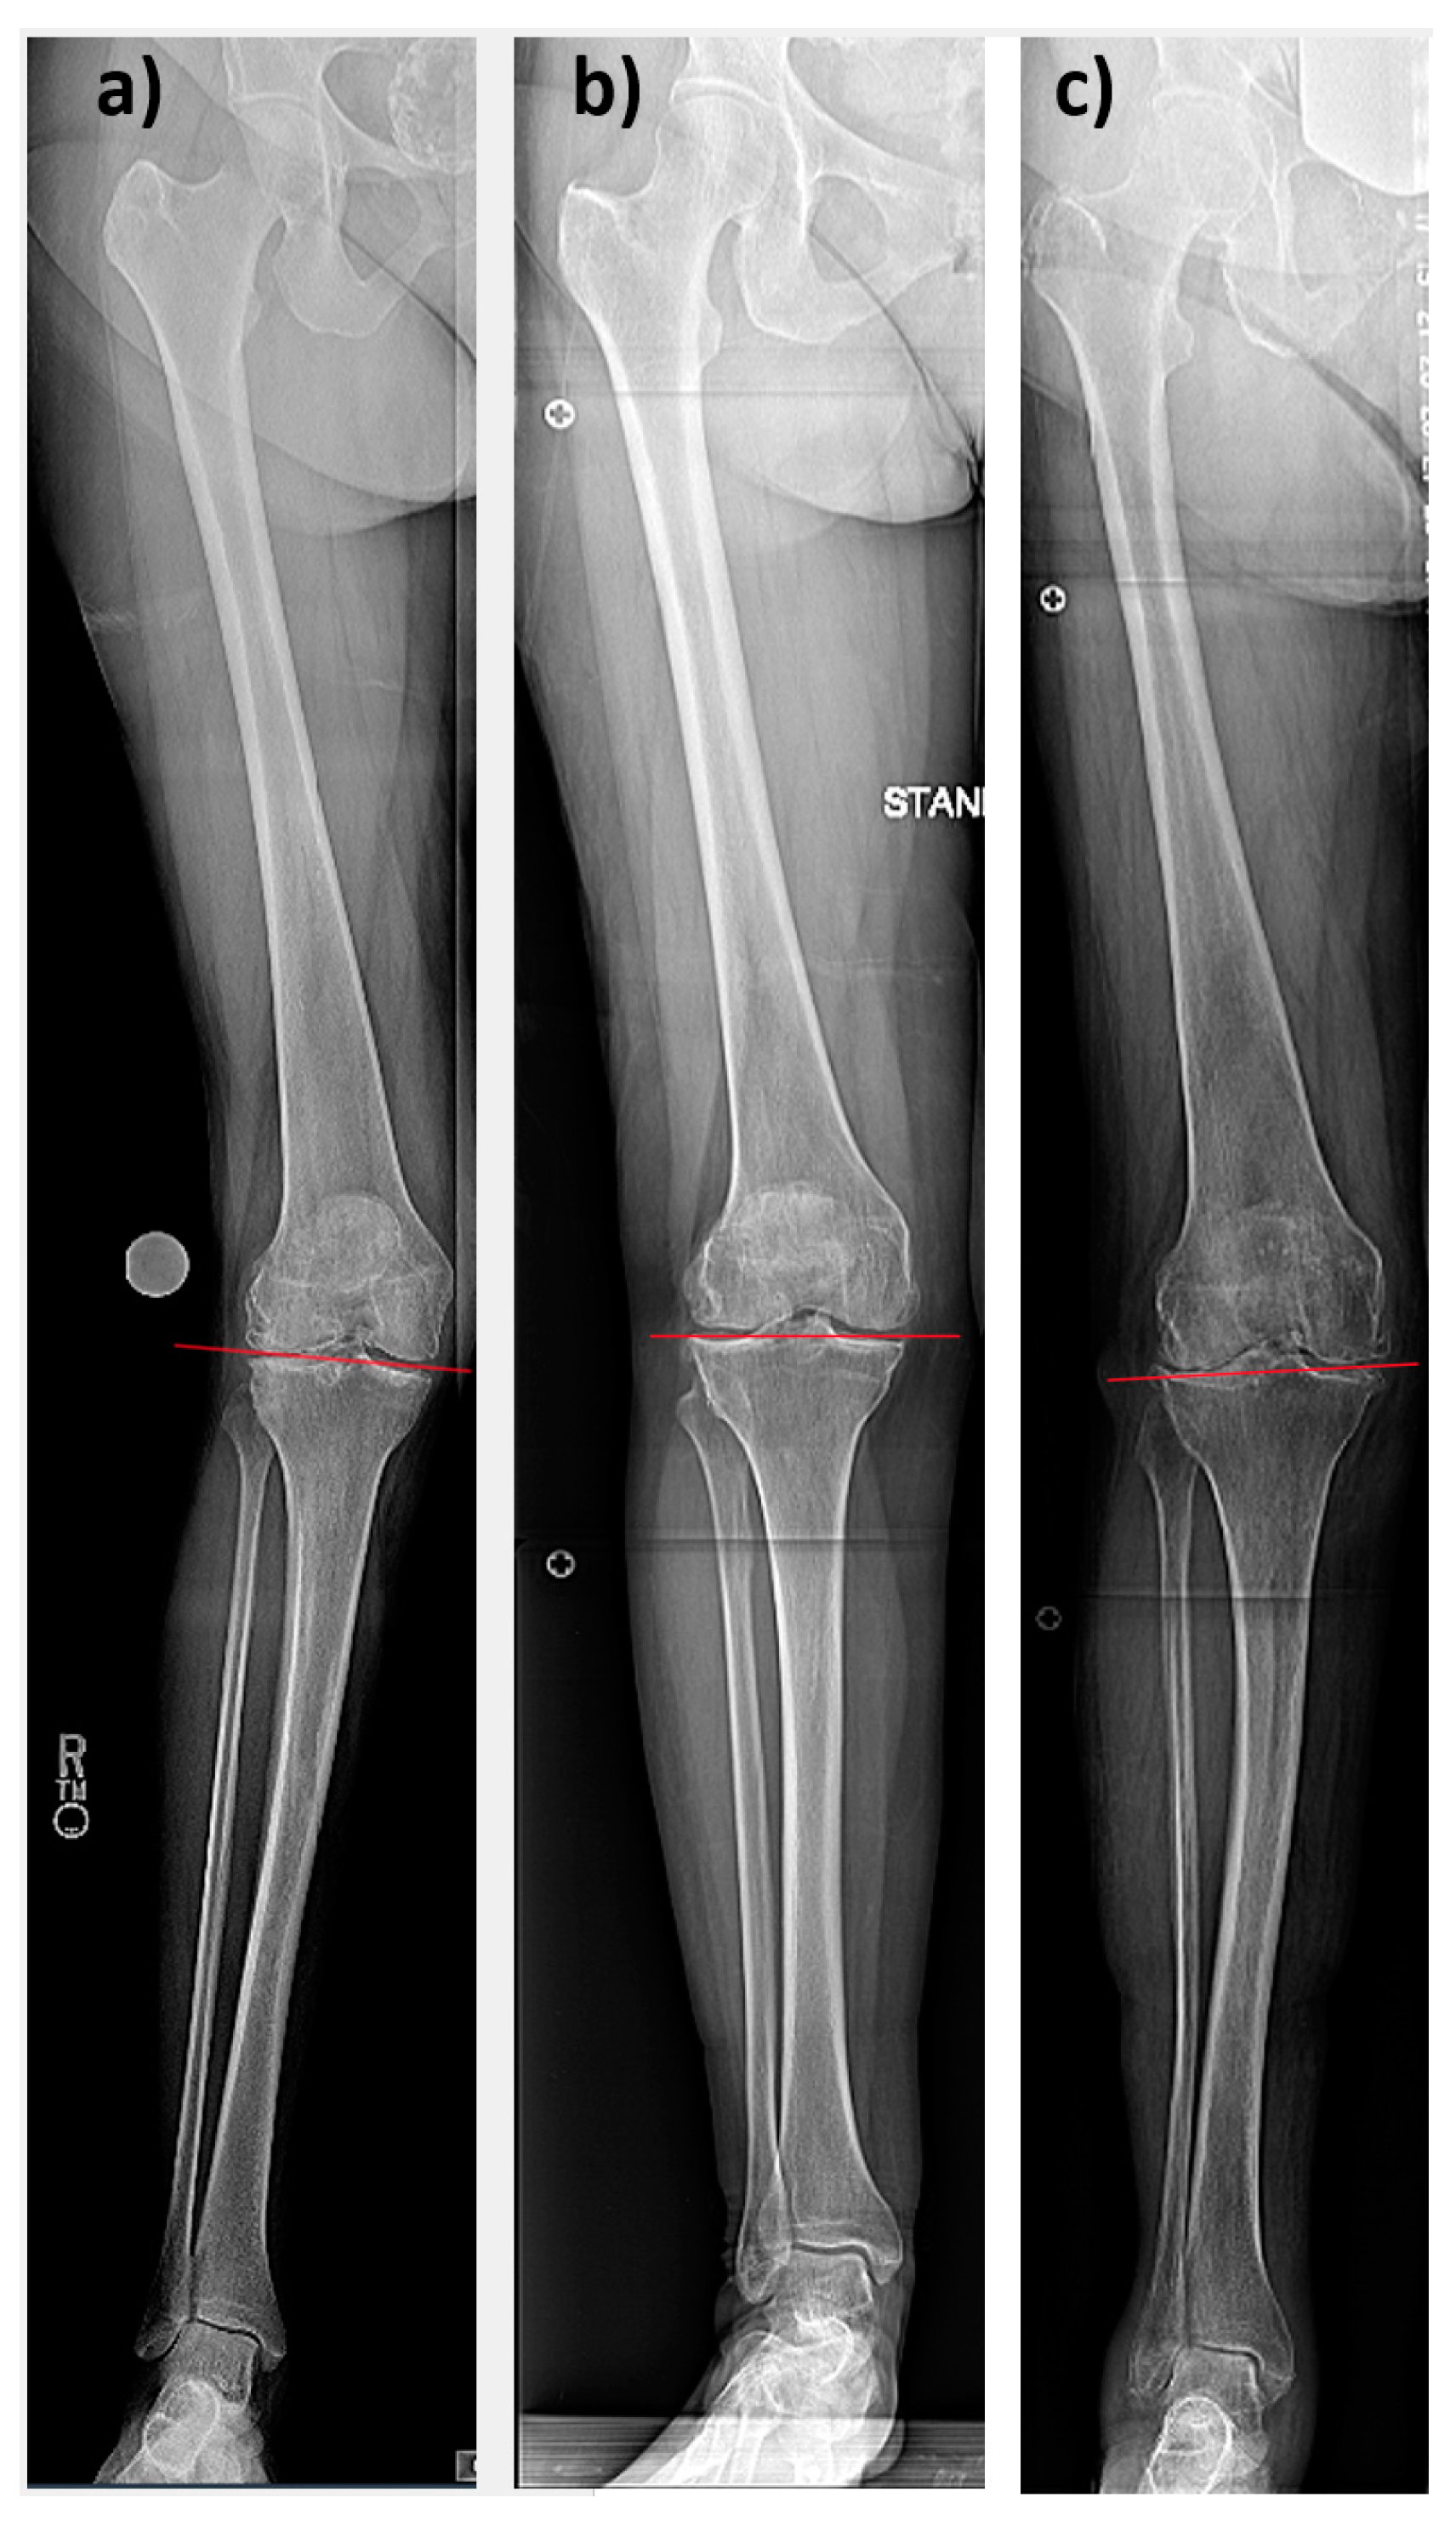

Figure 2.

Hip-to-ankle standing radiographs of right knees. All knees are valgus aligned. Red lines schematically show joint line obliquities (JLO) for (a) CPAK group III with a distal apex, (b) CPAK group VI with a neutral apex, and (c) CPAK group IX with a proximal apex.